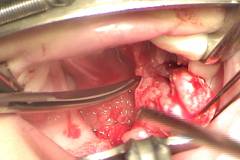

4. La fractura del Hamulus quita tensión a la sutura en la línea media y reduciendo el riesgo de dehiscencia, y no tiene ningún efecto negativo como lo mencione anteriormente. (Fig 7).

Figura 7. Liberación completa de la arteria palatina posterior y fractura del Hamulus.